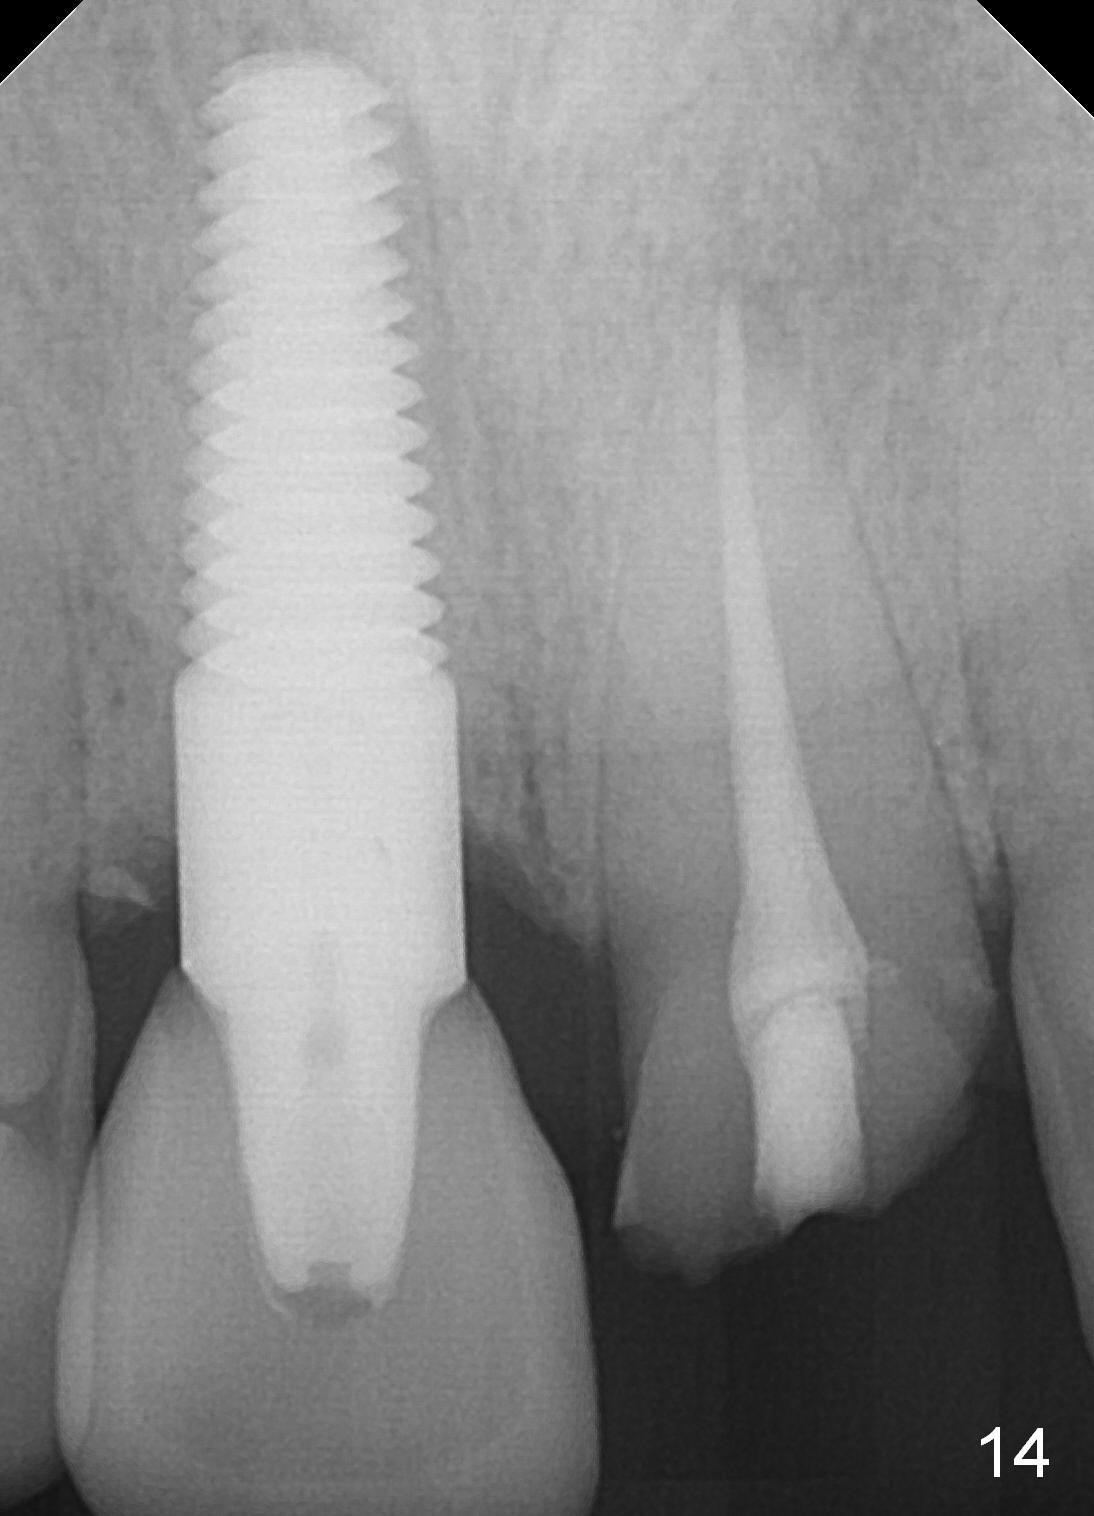

A 55-year-old man has severe pain on the upper right central incisor (Fig.1 *) after biting on a piece of bone. PA confirms crown fracture (Fig.2 <), extending subgingivally (Fig.3 >>). Osteotomy forms using a 2 mm pilot drill and 2.5-3.5 mm reamers (Fig.4). A 5x17 mm Tatum tapered implant is placed, autogenous bone placed in the buccal gap, sutures placed for wound approximation and 3.5 mm 20º angled abutment installed (Fig.5). An immediate provsional is fabricated (Fig.6), cemented and splinted (Fig.7).,

When the patient returns 3 years 10 months post cementation, the tooth #9 fractures (Fig.13,15,16), and receives root canal therapy (Fig.14). The dark gingiva could be avoided if the implant is placed more palatally and smaller in diameter (Fig.15,16).